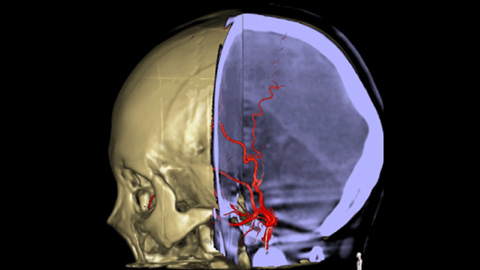

Die Möglichkeit zur Darstellung der vaskulären Anatomie und endovaskulärer Materialien im Submillimeter-Bereich verbessert die Erfolgschancen und erhöht die Behandlungssicherheit. XperCT bietet CT-artige Bilder, die direkt in der Neuro Suite erfasst werden und die Identifizierung diskreter Weichgewebeläsionen erleichtern. Eine Kontrolle des Behandlungserfolgs ist somit noch im Untersuchungsraum möglich. VasoCT bietet 3D-Bildgebung mit hoher Auflösung, die wichtige zerebrovaskuläre Strukturen darstellt und so die räumliche Beurteilung von Gefäßen im Weichgewebe auf höchstem Niveau unterstützt.

3D-RA liefert in wenigen Sekunden eine volumetrische Darstellung und unterstützt so die Beurteilung von Position, Größe, Hals und Schweregrad des Aneurysmas für die Behandlungsplanung. Darüber hinaus bietet 3D-RA Volumendaten mit hoher räumlicher Auflösung und gleicht Patientenbewegungen automatisch aus.